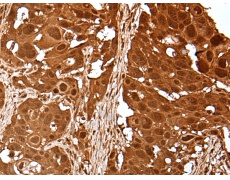

IHC positive control: |

Human tonsil and human breast cancer |

IHC Recommend dilution: |

25-100 |